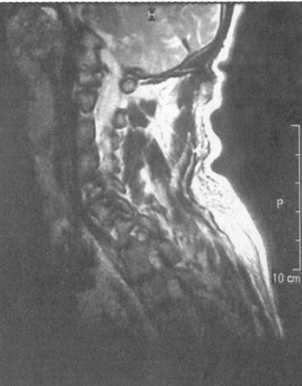

Ценную информацию о состоянии вывихнутых позвонков и спинного мозга дает

МРТ (рис. 2.6, 2.7). МРТ позволяет определить наличие зон ишемии в спинном

мозге (рис. 2.8, 2.9), состояние ликвородинамики (рис. 2.10).

Рис. 2.10. Компрессионный перелом С6 позвонка со смещением его

кзади

и нарушением ликвороциркуляции на данном уровне